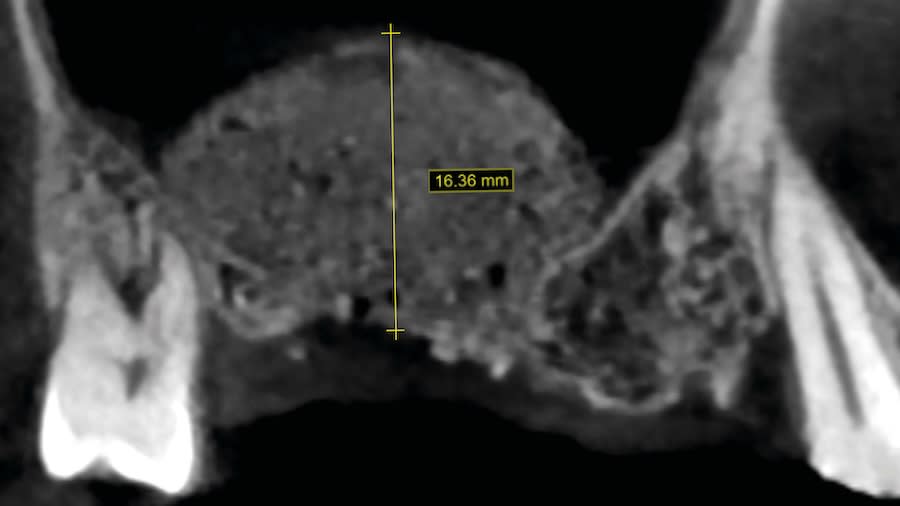

Case 1 (Figure 3 through Figure 24) depicts a 3-year follow-up of combined osseodensification sinus protocol IV in a severely resorbed maxillary ridge with ≤0.5 mm bone height in molar sites and horizontal deficiency at the first premolar site, using a two-stage approach for implant placement.

Step 1: Measure bone height at the osteotomy site on the CBCT. Measure ridge clinical width. A minimum of 7 mm alveolar ridge width is needed. Perform horizontal incision 2 mm to 3 mm palatally from the planned osteotomy site and elevate the flap using regular techniques of the clinician’s choice.